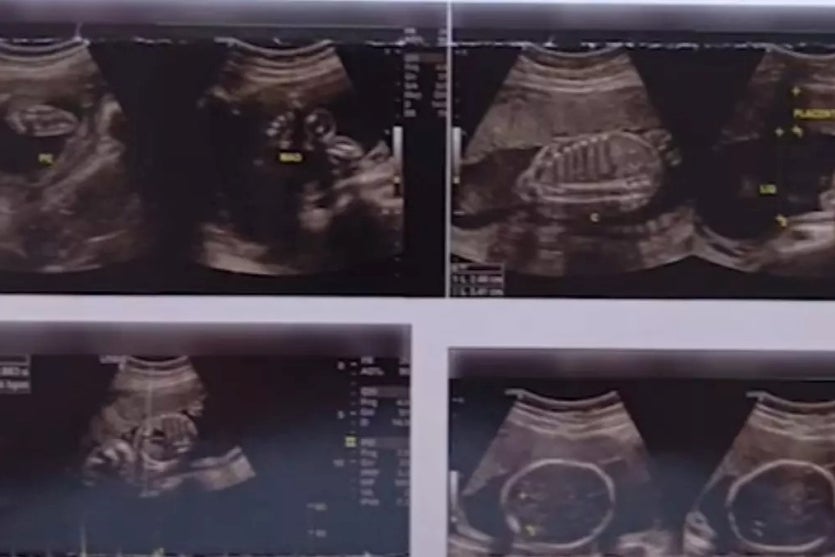

Um homem, de 48 anos, que realizou uma ultrassonografia abdominal para a identificação de hérnias teve um diagnóstico, no mínimo, inesperado ao obter o resultado dos exames. Ele, que fez o procedimento em uma clínica de Londrina, no Norte do Paraná, recebeu um laudo de gravidez, inclusive com imagens do bebê reveladas no exame.

“Fui fazer um ultrassom para ver duas hérnias, que é caso de operação. Só que chegou o resultado do exame e diz que eu estou grávido, vou ter um filho. No exame consta meu nome, tudo certinho, estou grávido”, disse o paciente.

A princípio a confusão se deu pela troca de imagens da ultrassom com o de uma mulher, que realmente estava grávidas. A clínica responsável pelo procedimento emitiu uma nota, nesta sexta-feira (20), onde diz que esse tipo de situação nunca havia ocorrido antes na clínica e que procurou o paciente assim que identificou que o resultado estava errado.